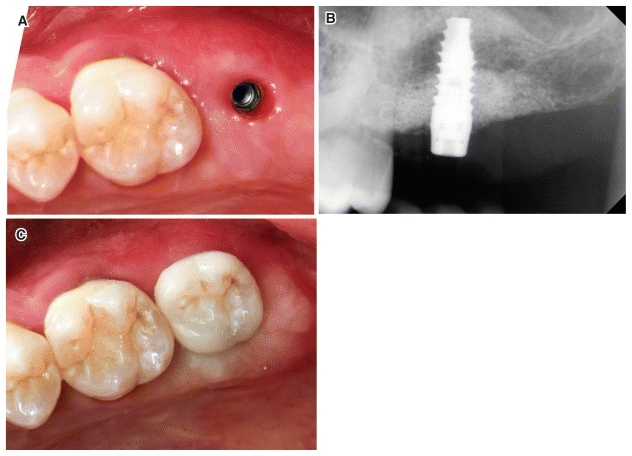

The patient was recalled 6 months after the first operation, and a new CBCT scan was performed to evaluate the maturation of the bone graft and plan the implant insertion. The scan showed a 3D increase in the residual alveolar process and a reduction in the periodontal defect (Figs. 3a–3b). The digitally calculated distance between the bone crest and the maxillary sinus floor was 8 mm. Therefore, a 3-mm crestal elevation was planned at the same time as the insertion of a 10-mm-long implant with a transmucosal portion of 1.8 mm (3c). Loss of the vestibular fornix following the first operation appeared to be insignificant and did not require corrective surgery. The patient underwent a new oral hygiene session one week before the operation. After loco-regional anesthesia (40 mg/ml of articaine + 0.01 mg/ml of adrenaline), a sagittal incision was made in the crest without vertical releases, extended mesially to the two elements adjacent to the defect, and followed by a full-thickness dissection of an envelope flap. The d-PTFE membrane was exposed, and the fixing screws were removed. The membrane, which appeared particularly adherent to the underlying hard tissue, was removed using Lucas elevators and curettes (Fig. 4a), following which, the two support screws were finally removed. A distance of 4 mm between the new osseocrestal plane and the CEJ of the distal portion of tooth 26 was measured with a millimeter probe (Fig. 4b). A crestal access was created in a prosthetically guided position, and an implant site was prepared up to the floor of the maxillary sinus. Subsequently, access to the sinus was achieved using a traumatic rotating drills. (PRO SCV Sinus Lift, Resista, Verbania, Italy), A biomaterial, carbonate apatite and cross-linked hyaluronic acid mixture, was grafted (Hyadent BG, Regedent AG, Zurich, Switzerland). An implant with a 1.8-mm intramucosal neck was inserted (Prama, Sweden & Martina, Due Carrare, Italy). The neck was placed in a supracrestal position, and a minor correction of the bony contour of the alveolar process was performed with high-porosity porcine-derived carbonate apatite (Fig. 4c). Subsequently, a soft tissue augmentation technique was performed with a CTG derived from the deepithelialization of a free gingival graft taken from the palate in the area adjacent to teeth 16 and 17. The mesiodistal and apico-coronal dimensions of the CTG were approximately 14 and 11 mm, respectively, while the thickness was 2 mm (Fig. 4d). The graft was drilled in the center, in the position of the neck of the implant, using a rounded punch (diameter, 2.5 mm), and stabilized around it (Fig. 4e). The flap was sutured over the graft using 5-0 monofilament PGA sutures; a medical collagen fleece was adapted and sutured at the sampling site on the palate (MediCipio C, Medichema GmbH, Chemnitz, Germany) (Fig. 4f).

After an additional 5 months of healing, an X-ray control was performed, followed by a flapless uncovering of the implant using a rotating punch. A transmucosal healing abutment was placed. Two weeks later, the supracrestal soft tissue appeared free of inflammation, and a pink mucous cone was observed over the prosthetic Ultra thin Threaded Microsurface (UTM) neck connection of the implant (Fig. 5a). CTG integration and enhanced supracrestal soft tissue were noted. Radiologically, the graft was distinguishable due to increased supracrestal hard tissue and an elevated maxillary sinus. Additionally, there were no local peri implant infections, and the periodontal bone defect affecting the distal portion of tooth 26 was resolved (Fig. 5b). A PPD of 3 mm without recession(resulting in a CAL of 3 mm) was measured at the disto-buccal and disto-palatal aspects of the first molar. A CAL gain of 6 mm was obtained when compared to the measured variable at the time of the first operation. Two weeks after reopening, a digital impression of the implant position and soft tissue tissues were taken, and a screw-retained lithium disilicate crown was fabricated (Fig. 5c). The patient was then recalled 18 months after the prosthesis placement and examined with intra oral X-rays. The physical examination revealed good oral hygiene and the absence of gingival inflammation, with the soft tissue appearing stable around the prosthetic restoration (Fig. 6a). Radiologically, the hard tissue was maintained in the peri implant region and the distal portion of tooth 26 (Fig. 6b). The timeline of the clinical case is shown in Figure 7.